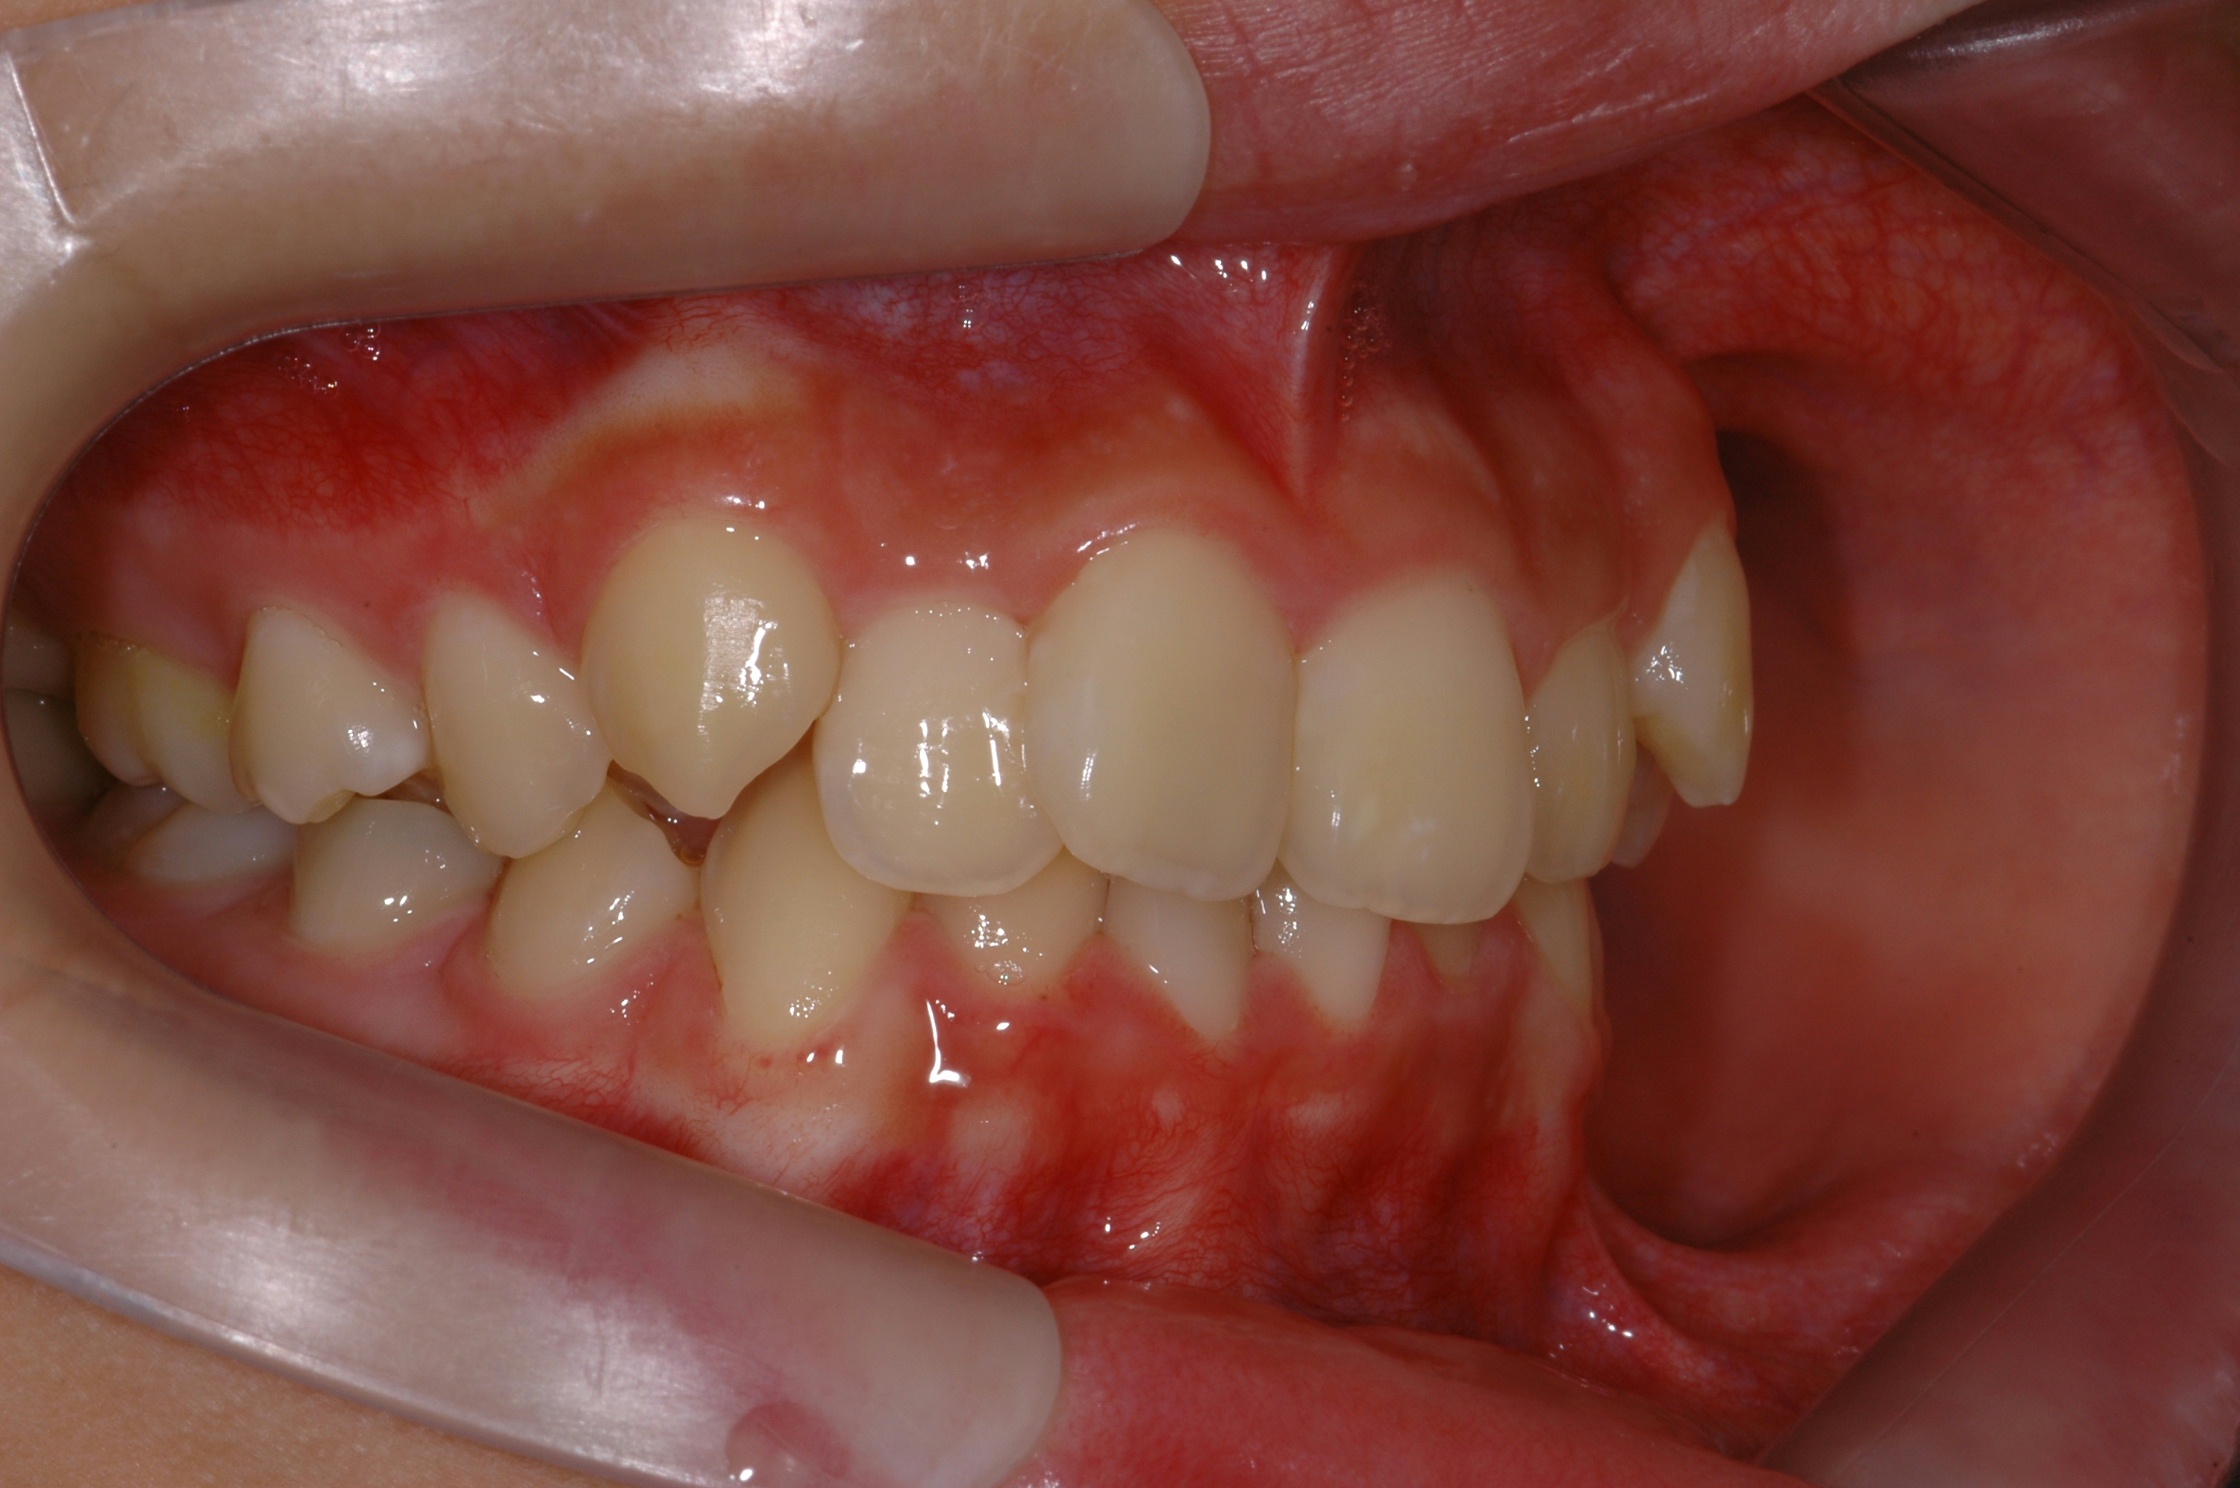

치료 후 사진입니다.